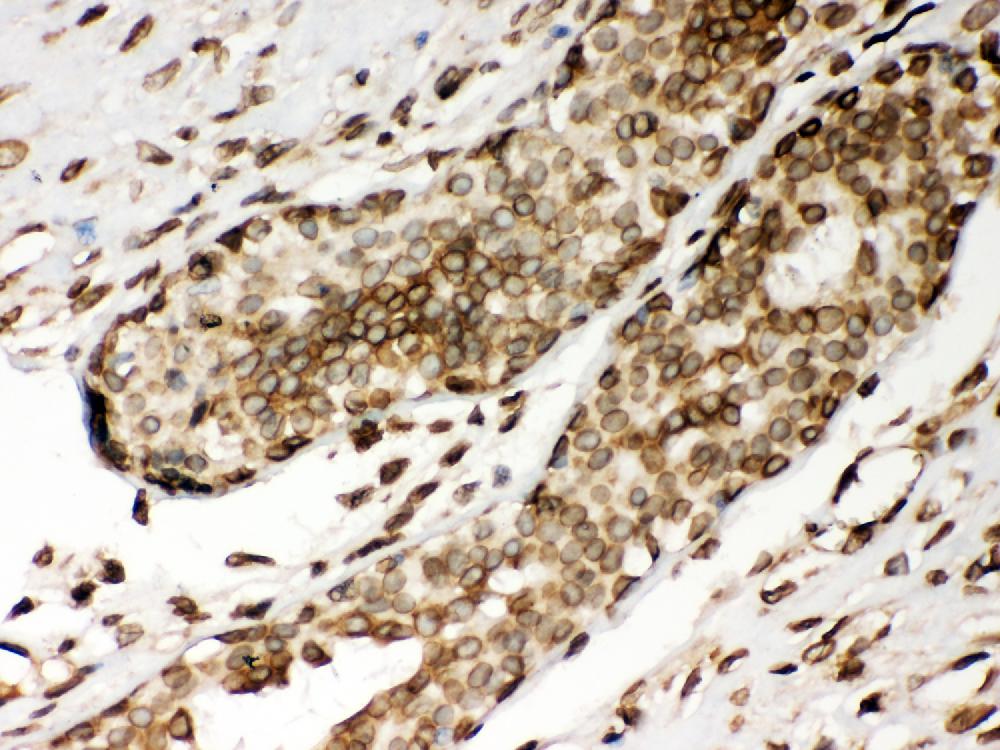

IHC analysis of Lamin A/C using anti-Lamin A/C antibody (PB9280).

Lamin A/C was detected in a paraffin-embedded section of human mammary cancer tissue. Biotinylated goat anti-rabbit IgG was used as secondary antibody. The tissue section was incubated with rabbit anti-Lamin A/C Antibody (PB9280) at a dilution of 1:200 and developed using Strepavidin-Biotin-Complex (SABC) (Catalog # SA1022) with DAB (Catalog # AR1027) as the chromogen.